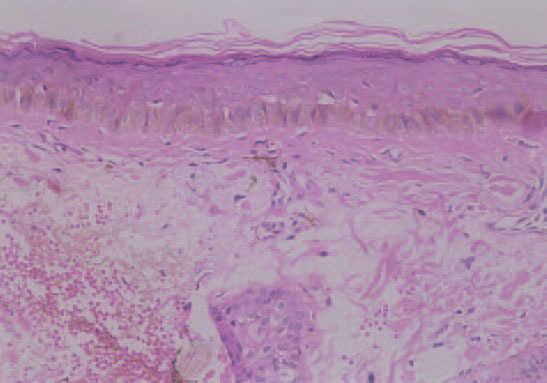

Varón de 62 años, con el único antecedente de una bronquitis crónica leve tratada con broncoinhaladores. Consultó por presentar una lesión pigmentada de 6 años de evolución, asintomática, de crecimiento progresivo, que se extendía desde el ángulo externo del ojo izquierdo hacia la mejilla. En la exploración se observó una mácula discrómica de 2 cm de diámetro, de contorno geográfico y límites netos, que afectaba a ambos párpados del ojo izquierdo en su canto externo, quedando a 1 mm del borde libre palpebral (fig. 1). La biopsia de la lesión mostró melanocitos atípicos aislados en la capa basal de la epidermis y alguno de aspecto pagetoide en los estratos más altos (fig. 2).

Fig. 2.—Aspecto histológico de la lesión previo al tratamiento. (Hematoxilina-eosina, ×80.)